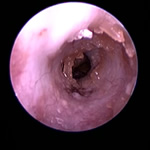

角化症、脂漏症という生まれつきの体質を持ったワンちゃんは耳垢が多くなりがちです。また、角化症、脂漏症の長毛種となれば、耳の中に毛が生えた犬種も多く耳道から耳垢を排泄しにくくなります。それらが原因で耳に汚れがたまります。また長毛種はトリミングに行く回数も多く、耳を洗う機会が多くなります。こんな負の連鎖があり、いずれも耳を悪くする大きな原因になります。その全ての要因に対処しなければ耳の病気は解決しません。写真は鼓膜手前に耳垢や毛が蓄積し、通常の耳洗浄ではきれいにできない状態です。セカンドオピニオンで来院されるワンちゃんで最も多い病気の1つです。

フレンチブルドックはアトピー性皮膚炎、食物アレルギー、脂漏症、甲状腺機能低下症など皮膚病になりやすい犬種です。さらにフレンチブルドックの耳道はもともと入口がとても広く、鼓膜手前で極端に狭くなっています。もし、これらの皮膚病を発症すると外耳炎が起こりやすくなります。外耳炎が起こると耳垢が溜まり、耳洗浄による耳道刺激があったり、微生物の増殖など負のサイクルに陥ることがあります。さらに耳道周囲の体毛が耳の中に入りやすいため、鼓膜手前に毛が蓄積します(写真)。体毛、微生物が増殖した耳垢、皮膚病の放置といった悪化因子が重なると非常に重度の中耳炎になります。